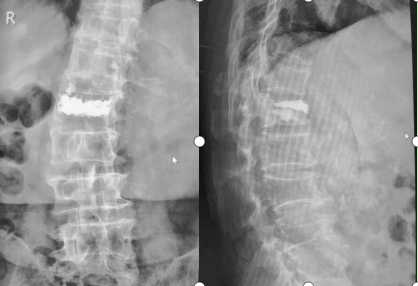

4.骨質(zhì)疏松性骨折椎體成型術(shù)后